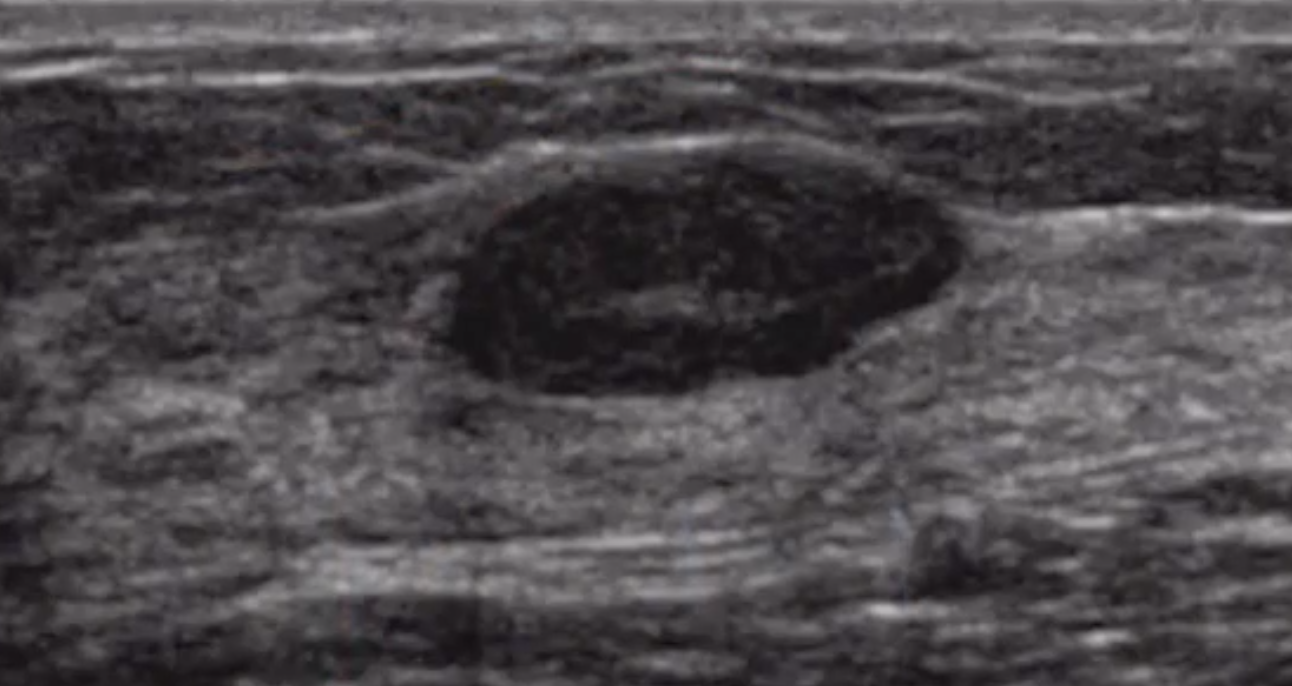

Lymph Nodes

• Commonly in posterior third of breast